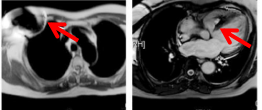

另外,即使是MRI兼容的心脏起搏器,在进行心脏检查时依旧会有伪影,影响检查结果。